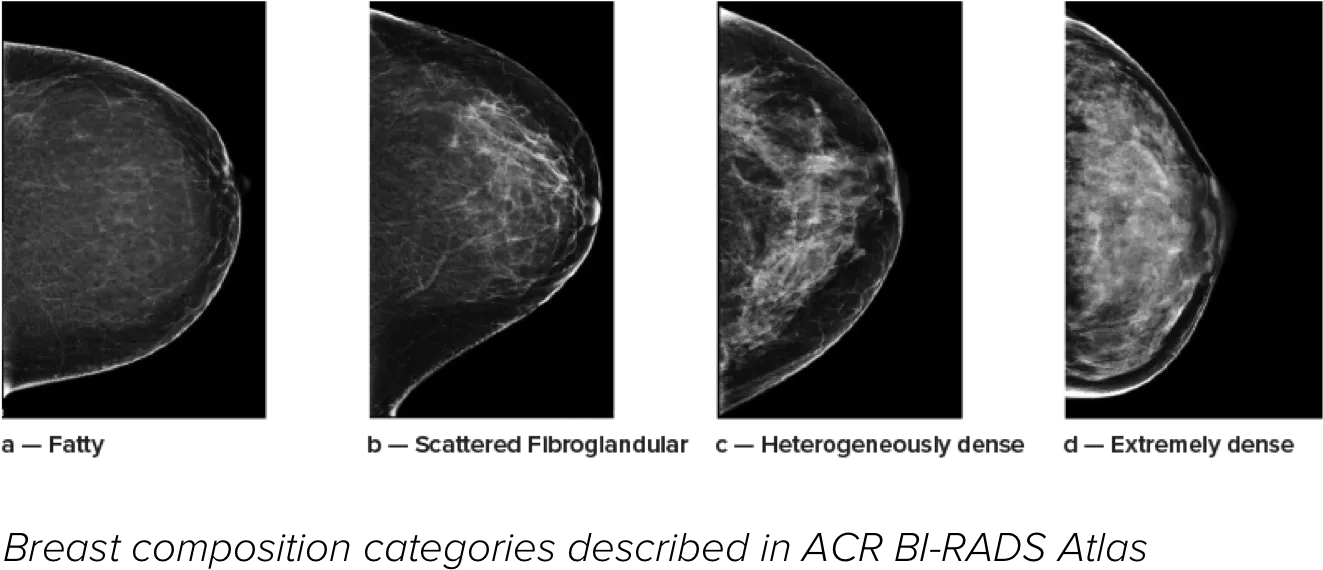

Sabe-se que uma maior densidade mamária aumenta o risco de desenvolver cancro da mama.1 Consequentemente, é fundamental uma análise precisa e não enviesada. O software de tecnologia Quantra, com aprendizagem automática, analisa a distribuição e a textura do tecido parenquimático, tanto através de imagens de 2D™ como de tomossíntese. Este categoriza a mama em quatro categorias de composição da mama, em conformidade com as diretrizes da American College of Radiology (ACR) BI-RADS Atlas 5th Edition.2

8. Breast composition categories as described in ACR BI-RADS Atlas.